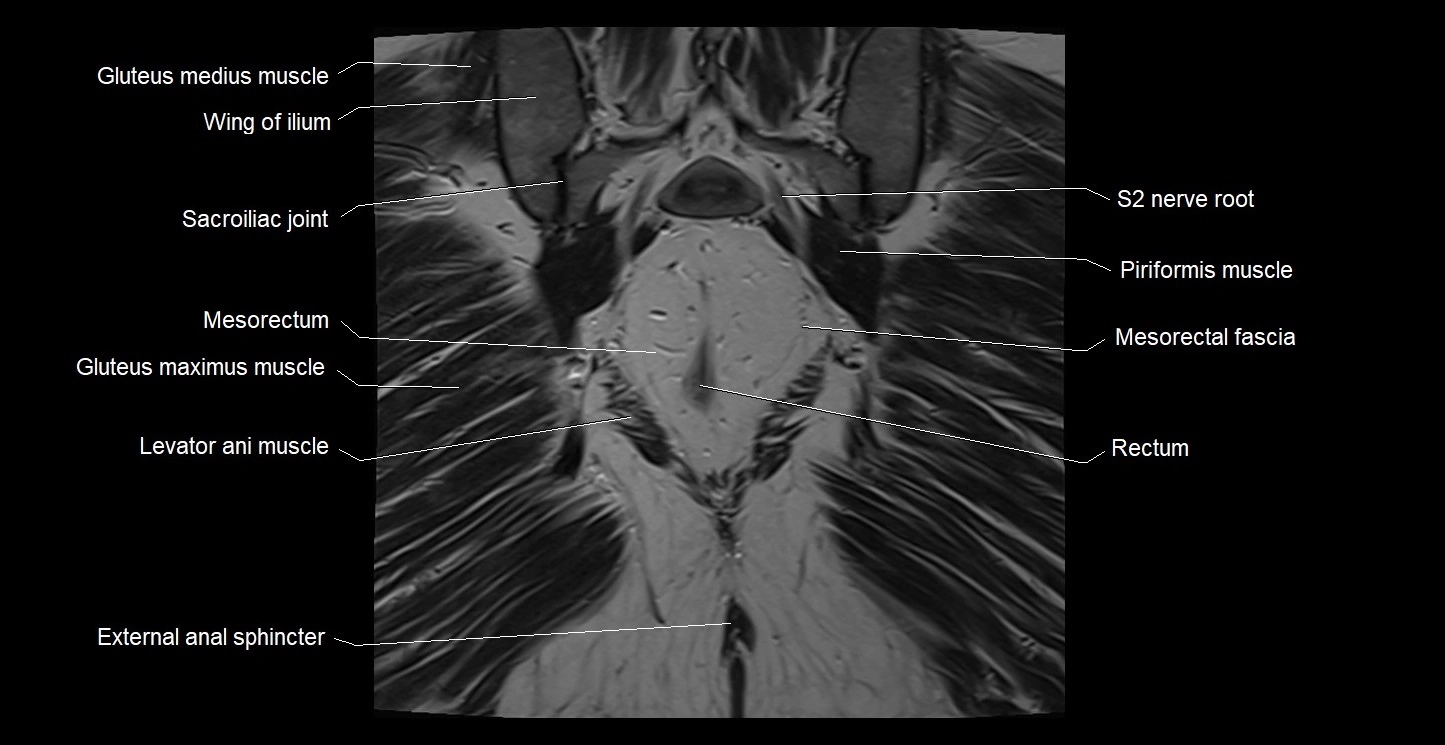

- External anal sphincter

- Gluteus maximus muscle

- Gluteus medius muscle

- Iliococcygeus muscle

- Levator ani muscle

- Mesorectal fascia

- Mesorectum

- Piriformis muscle

- Rectum

- Sacroiliac joint